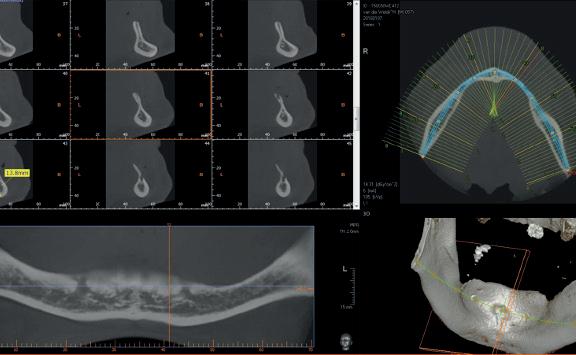

Voor het implantologisch onderzoek werd een CBCTscan (Trium CBCT, Acteon Frankrijk) vervaardigd van de edentate bovenkaak en in de software werd een planning gemaakt van 6 implantaten in de bovenkaak. De kaak kan opgedeeld worden in het front, tussen de 13 en 23 en de zijdelingse delen van de 14 t/m 17 en 24 t/m 27. Er dienen 2 implantaten in het front geplaatst te worden en 2 implantaten in de zijdelingse delen rechts en links, om een optimale verdeling van de implantaten (implant spread) te krijgen. De implantaten in deze casus werden gepland op posities 12, 22, 14, 24, 16 en 27. Tevens werd rekening gehouden met de krachtenverdeling óp de implantaten, deze zijn naar dorsaal toe forser dan in het front, daarom werd er gekozen voor brede implantaten (meer dan 5.0 mm in diameter) distaal en 4.0 mm diameter implantaten in het front. Voor de 16 was een crestale sinusbodemelevatie nodig en de 14 benodigde een kaakverbreding en verhoging.

Om de implantaten op de juiste vooraf geplande positie te implanteren, zijn er een aantal mogelijkheden (afbeelding 1 en 2). Eén daarvan is om de chirurgie guided uit te voeren, maar dat is lastig omdat de guide niet op elementen afgesteund kan worden. De guide dient dan met guide pins vastgeschroefd te worden, maar dat heeft als nadeel dat bij verplaatsing van de guide de implantaten niet op de juiste positie staan. Bij immediaat implanteren kan tegenwoordig gebruikgemaakt worden van meerdere stac-

2. Planning in de CBCT-software Acteon AIS